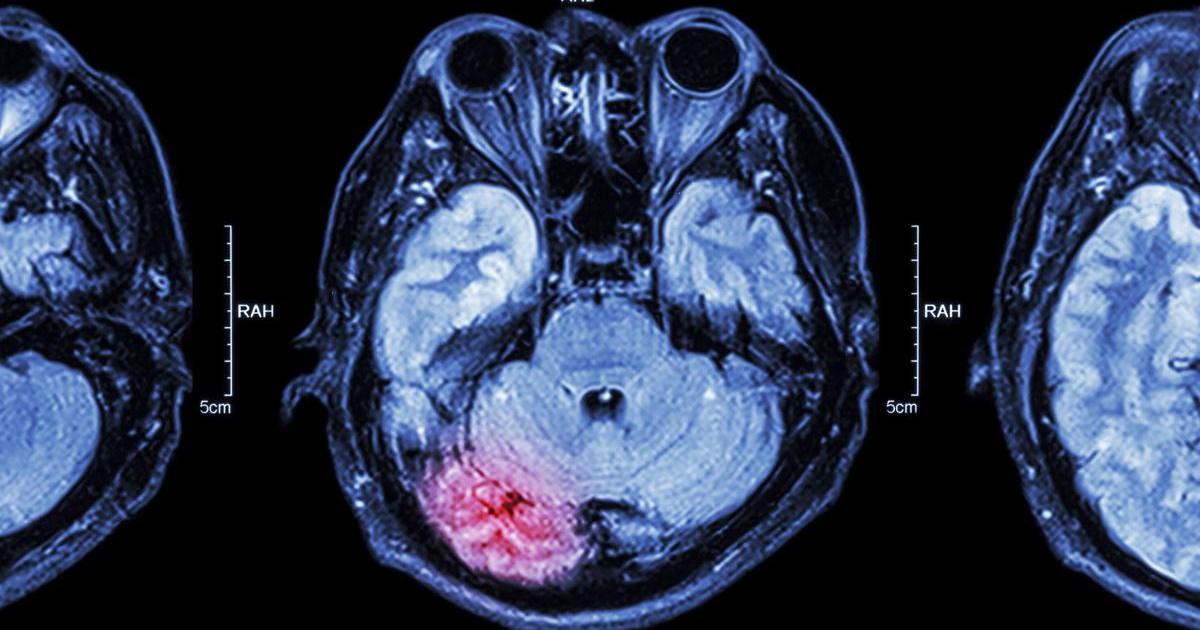

Subarachnoid Hemorrhage

A subarachnoid hemorrhage can lead to thunderclap headaches. This condition is a kind of life-threatening stroke that occurs when there's bleeding in the area around the brain. There are multiple possible causes of subarachnoid hemorrhages including head injuries, ruptured aneurysms, or a brain arteriovenous malformation. Arteriovenous malformations are knots or tangles of abnormal blood vessels responsible for connecting the brain's veins and arteries. One-third of patients who experience a subarachnoid hemorrhage survive and recovery well, another third survive but have a permanent disability, and the last third pass away. These types of strokes must be treated as soon as possible to stop the bleeding and restore the normal flow of blood in the brain. Like a cerebrospinal fluid leak, the thunderclap headache is related to cerebrospinal fluid. When there's bleeding into the area around the brain, the brain's lining becomes irritated. There's also increased pressure against the brain as well as damage to the brain cells.